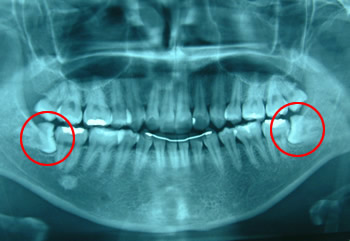

親知らずの抜歯顎関節症の治療、軽度の口腔外傷(歯の破折、脱臼、粘膜裂傷)口内炎などを診察します。

横向きに出てきた親知らずは汚れがたまりやすく、腫れる原因となります。

場合によっては、手前の歯に虫歯を作ったり、咬みあわせを崩すこともあります。